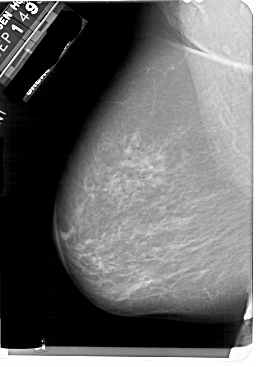

A_1858_1.LEFT_MLO

LEFT_MLO LINES 5491 PIXELS_PER_LINE 3826 BITS_PER_PIXEL 12 RESOLUTION 43.5 NON_OVERLAY